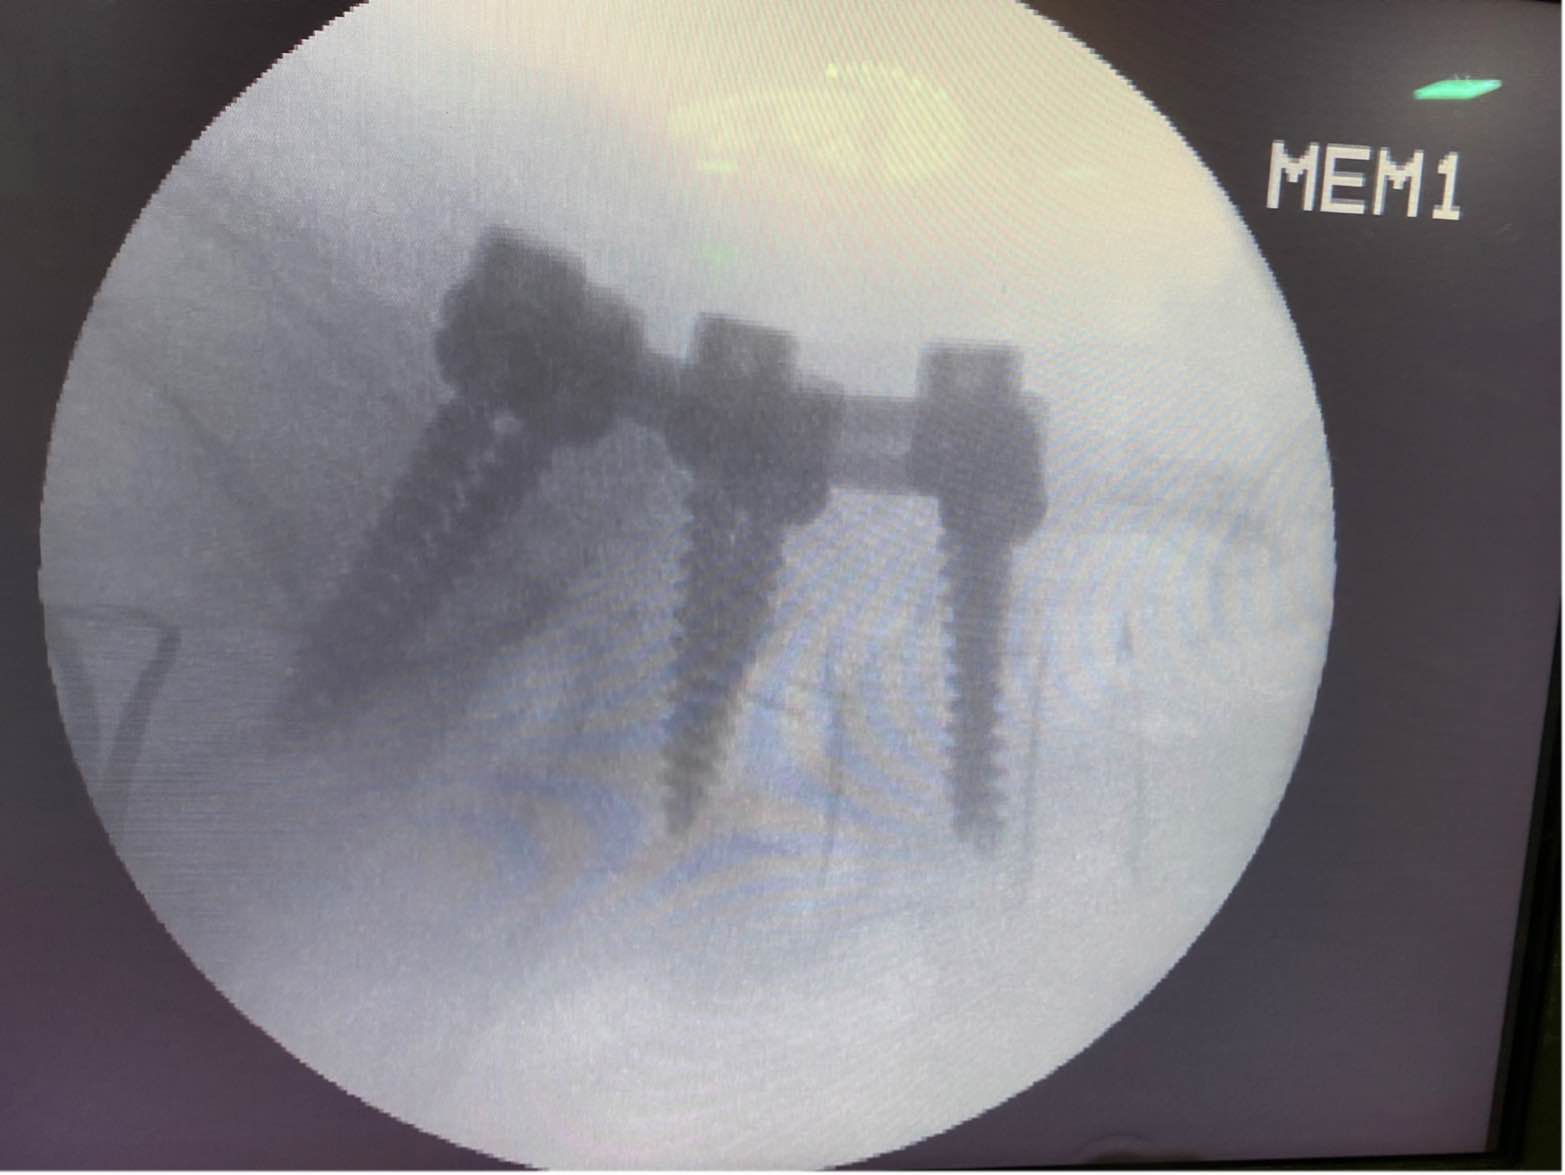

BEST SPINE SURGEON IN ANDHERI